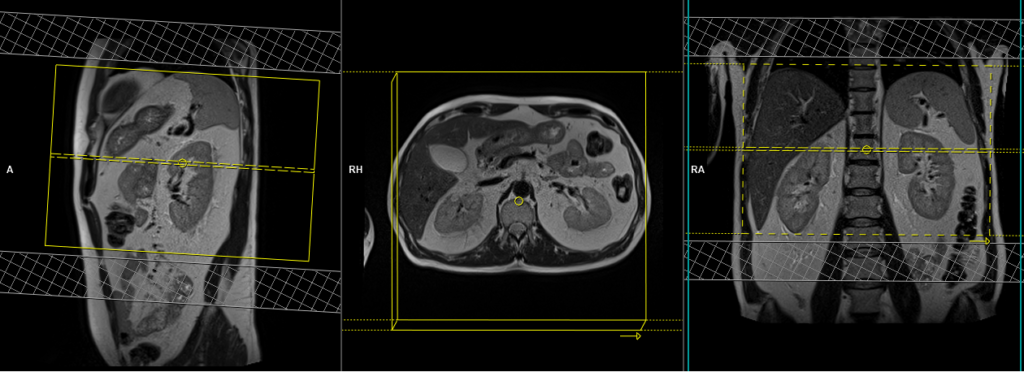

T1 VIBE DIXON 3mm axial BH pre GD(In-opposed phase and water sat)

Plan the axial slices on the coronal plane; angle the positioning block perpendicular to the thoracic vertebra. Check the positioning block in the other two planes. An appropriate angle must be given in the sagittal plane, perpendicular to the long axis of the kidney. Slices must be sufficient to cover both adrenals from the diaphragm down to the lower pole of the kidneys. Phase oversampling and, in the case of 3D blocks, slice oversampling must be used to avoid wrap-around artifacts. Using a saturation band on the top and bottom of the block will help to reduce artifacts from vascular pulsation and breathing. Instruct the patient to hold their breath during image acquisition.

When planning the axial breath-hold scans, it is crucial to utilize the breath-hold vibe coronal sequence. This is because during inhalation, the diaphragm exerts downward pressure on the liver, causing a shift in its position from the initial localizer scans. Therefore, to accurately capture the desired imaging area of the liver, it is important to account for this positional change by utilizing the breath-hold vibe coronal sequence.

Parameters

TR 6-7 | TE 2.39 4.77 | FLIP 10 | NXA 1 | SLICE 3 MM | MATRIX 320×320 | FOV 320-350 | PHASE A>P | OVERSAMPLE 20% | BH YES |